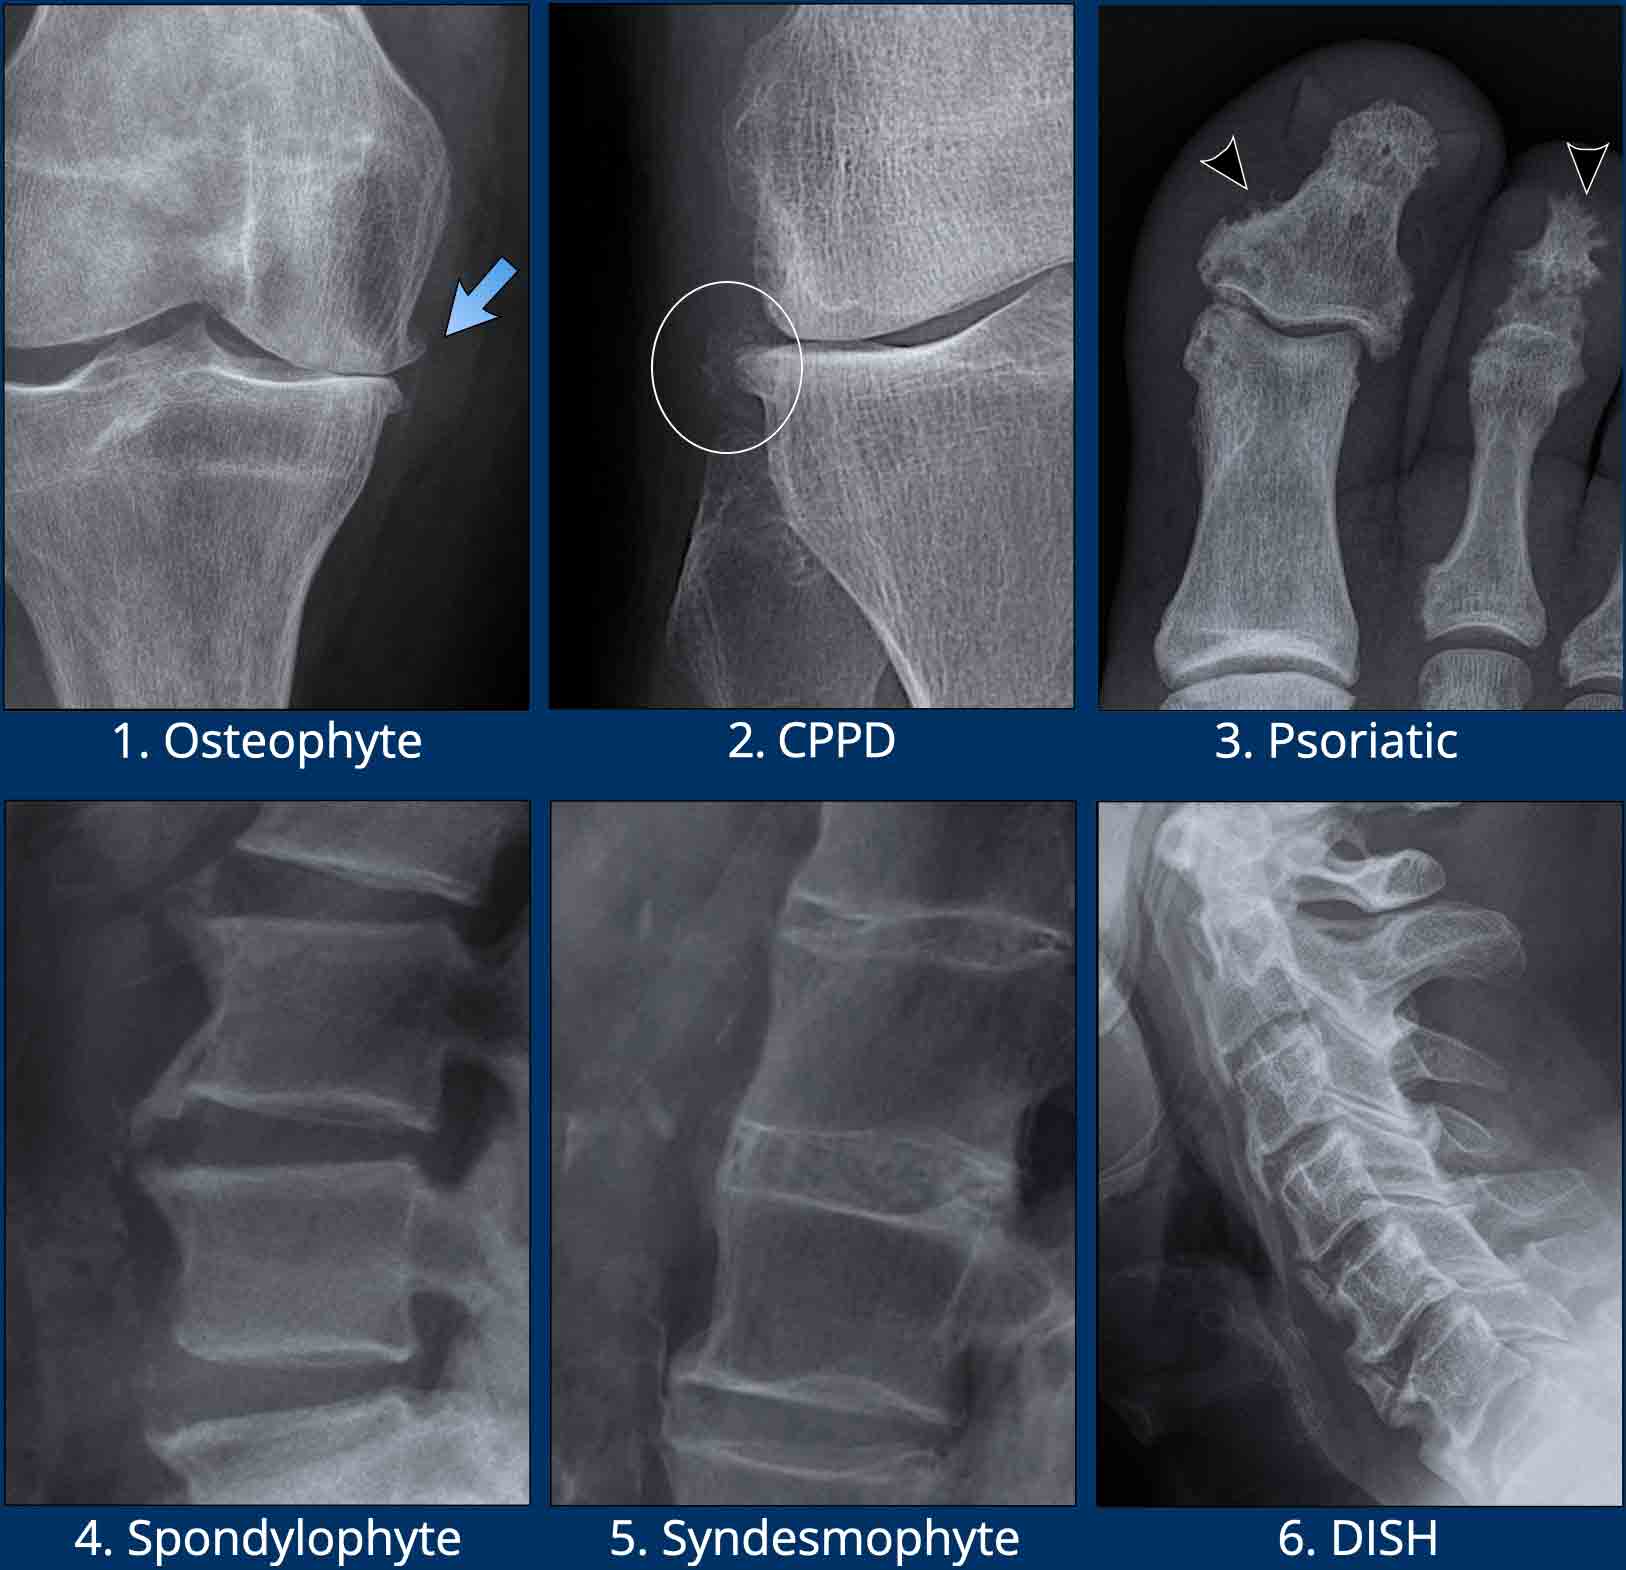

Раздел: Фотобанк решений